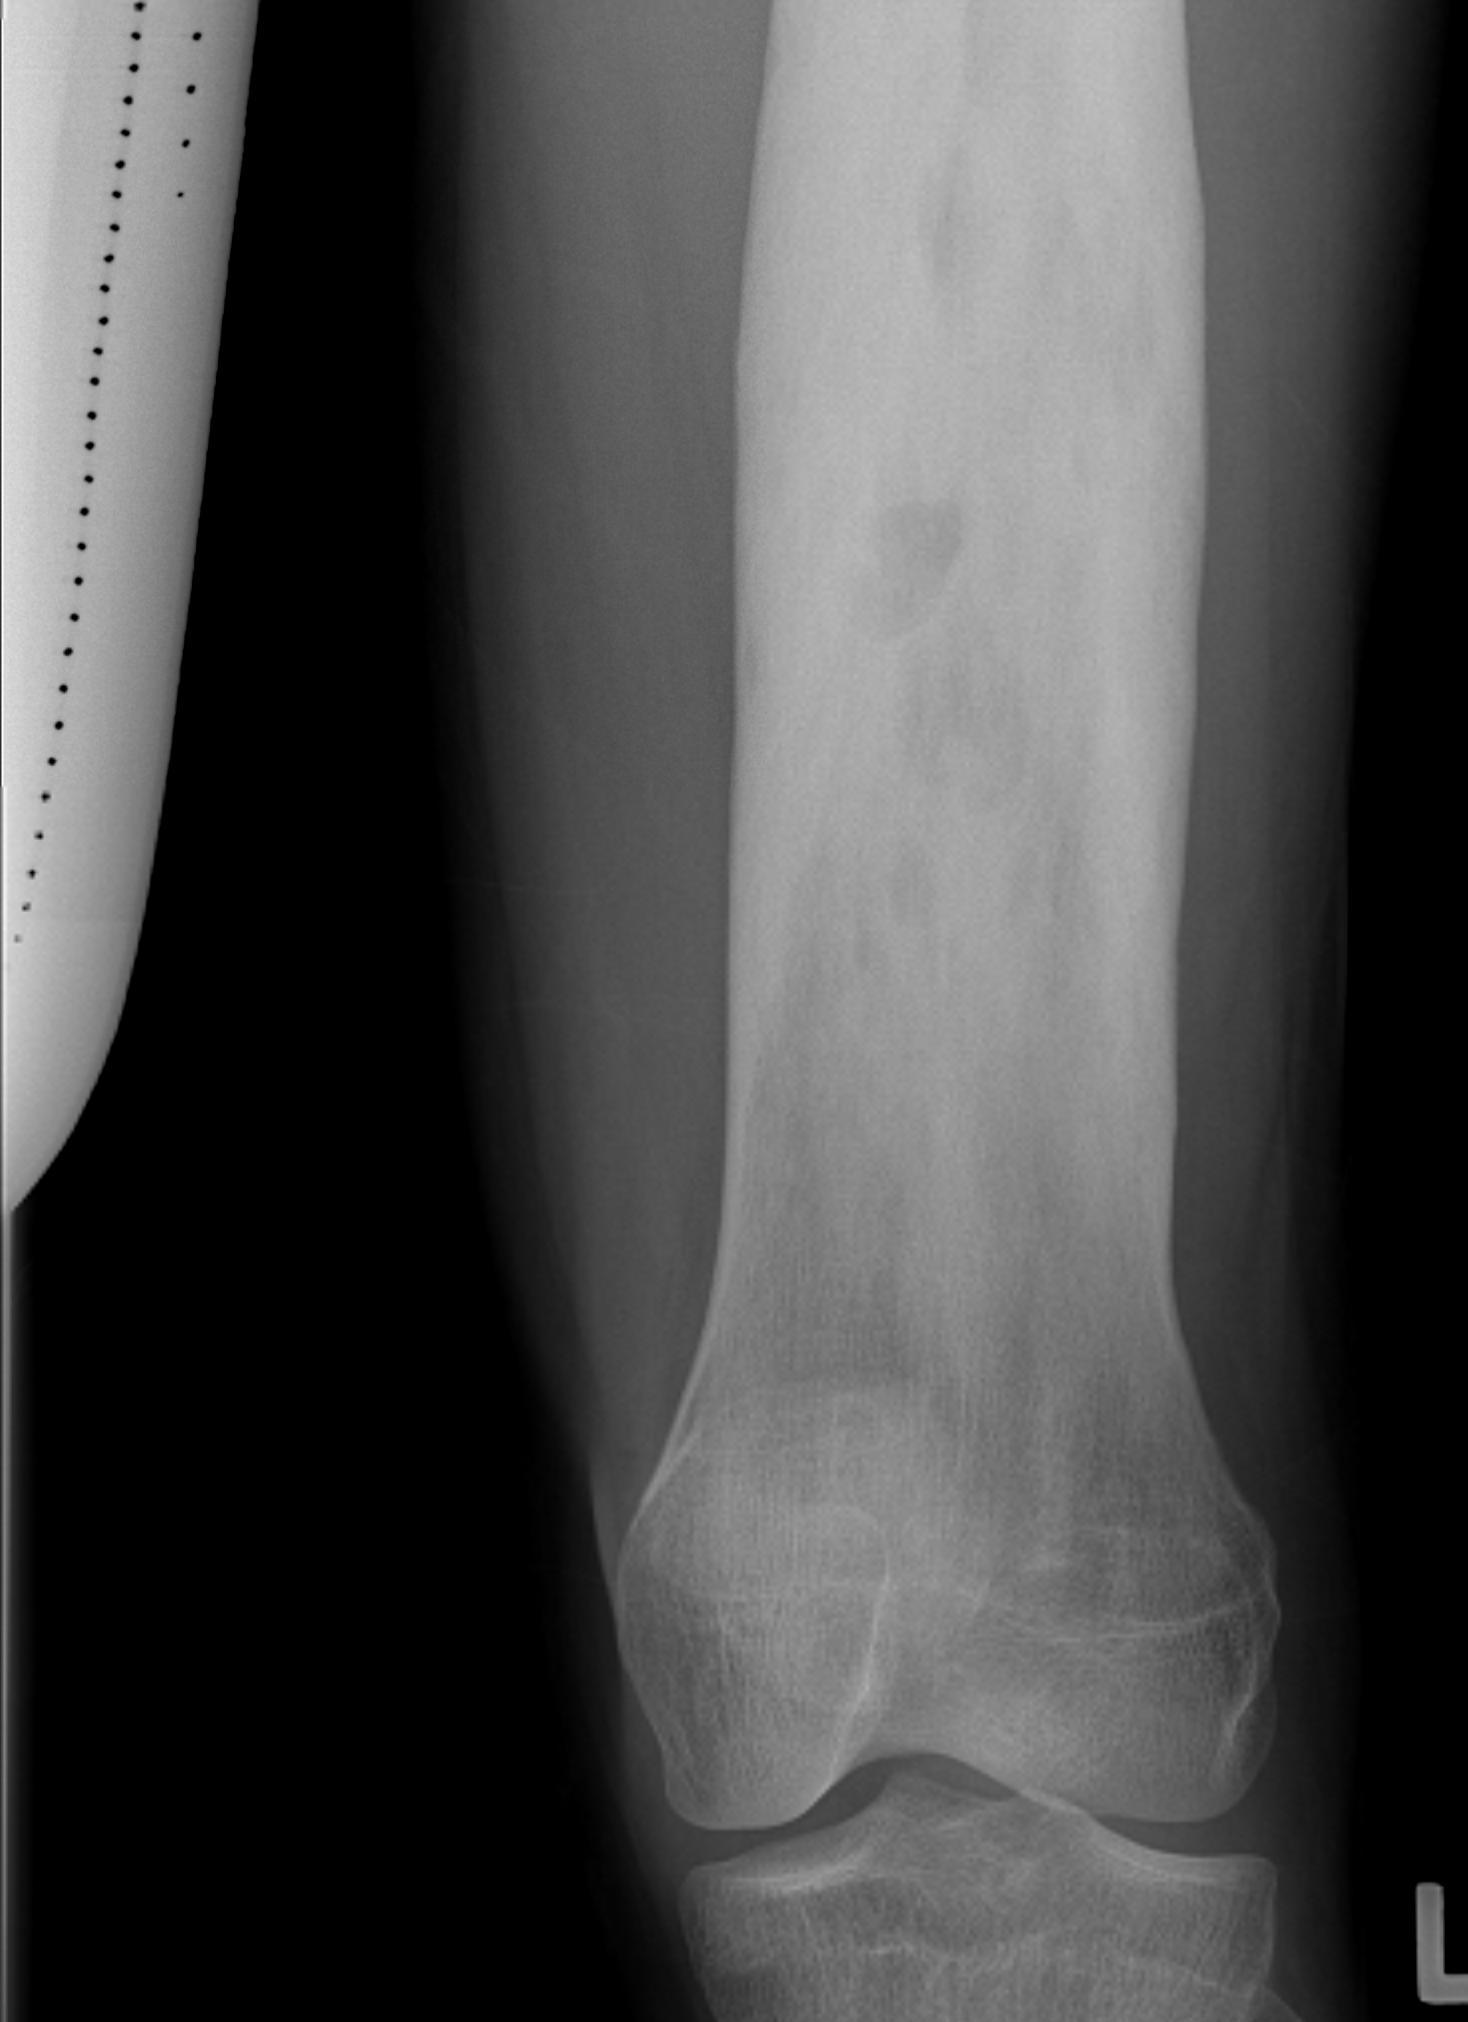

3. Condyles

- medial: incision through vastus medialis

- lateral: anterior to vastus lateralis